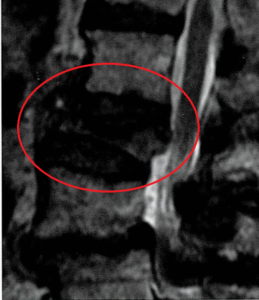

・MRIにおいてT2WI高信号や広範囲型低信号が骨癒合不全の危険因子である。

⇒T2WI高信号:浮腫が強く、骨癒合遅延、炎症持続

⇒広範囲型低信号:治癒していない範囲が広い。

・通常疼痛が改善してくる1か月程度を経過しても疼痛改善が乏しい場合は、動態撮影やCT、MRIでの評価を行い、骨折部の可動性を認めれば早期にBKPを検討すべきである。

⇒BKPの適応は少なくとも2か月以内に実施することが良いと考えられる。